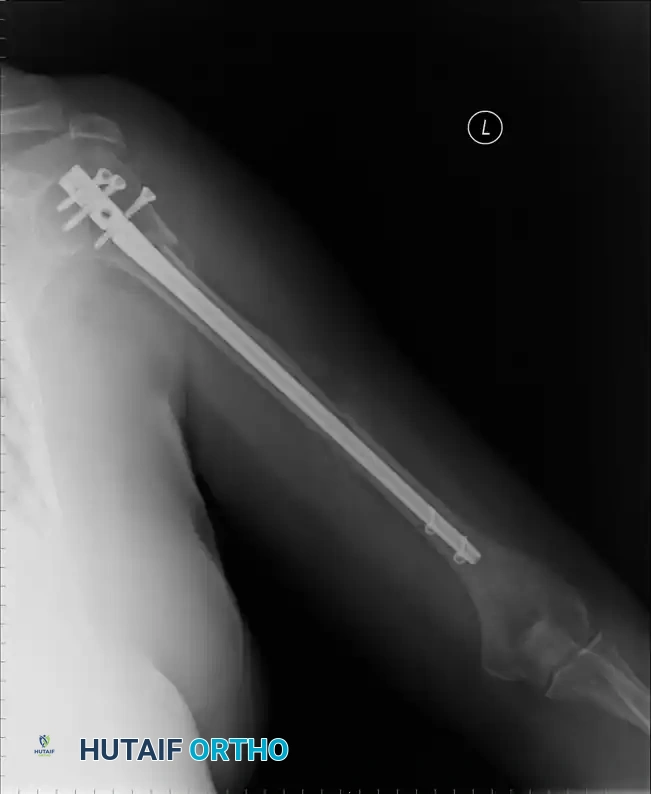

Percutaneous Pinning

Percutaneous pinning offers the distinct advantage of avoiding extensive soft-tissue dissection, thereby maximally preserving the blood supply to the humeral head. It is a minimally invasive, cost-effective technique. Jaberg et al. and Resch et al. have reported excellent outcomes using threaded pins or Kirschner wires.

Technique Overview:

* Closed reduction is achieved under fluoroscopy using traction, abduction, and manipulation.

* Pins are introduced percutaneously from the lateral humeral cortex, directed superomedially into the humeral head.

* Additional pins may be placed anteriorly to secure the lesser tuberosity or superiorly for the greater tuberosity.

* Warning: The axillary nerve is at risk during lateral pin insertion. Pins must be placed carefully, often utilizing a small stab incision and blunt dissection to the bone.